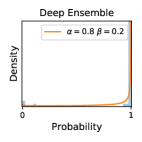

To model how different classifiers will respond to a given input , we assume that the prediction from classifier is sampled from a beta distribution that is characterized by two parameters by and . We further assume that is fixed to the same constant value for all ’s. Under this assumption, each input can be described by ( can be calculated since is fixed), easing further analysis. The Severity Level (SL) of the case represented by image can be characterized by the parameter . The larger the value of , the more severe the case of is. When and are close, the case is ambiguous as the distribution shifts towards being symmetric (i.e. signifying much disagreement among classifiers) rather than being one-sided (i.e. consensus among classifiers that is negative or positive). We provide a set of examples in Figure 2 and also Figure S.8 in the supplementary materials showing how the beta distribution can be used to capture diverse predictions given by an ensemble learner.

We conducted a case study on diagnosing diabetic retinopathy with ensembles of DL models. For benchmarking the performance of our ensemble-based solutions under the scheme described in Sec.3.3, we used two popular collections of diabetic retinopathy image data, the Kaggle Diabetic Retinopathy dataset [22] (hereafter referred to as “Kaggle-DR”) and the Messidor-2 dataset [23], each respectively consisting of and high resolution images. Diabetic retinopathy is graded into five SLs, as displayed in Figure 2. Following the problem setup used in previous papers [24], we trained models to distinguish the referable (SL2-4) cases from the non-referable ones (SL0 & SL1) (see Section B.1 for more detailed descriptions). We also tested our trained ensemble models on two o.o.d. image datasets (ImageNet [25] and CIFAR-10 [26]) to examine their capabilities of identifying o.o.d. inputs (see Section B in the supplementary materials).

5.1 Distribution of Uncertainty Scores

Distribution of Uncertainty Scores Across Different Severity Levels As explained in Section 3, each uncertainty metric essentially defines an order/ranking among the data points. We conducted an analysis to better understand what data will be assigned high uncertainty under a particular uncertainty metric . Picking out the highest ranked data points (), we calculated the ratio of data points from each SL. Figure 4 summarizes the results as box plots for the Kaggle-DR and the Messidor-2 datasets; additional detailed statistics can be found in Table S.1 in the supplementary materials. From the plot and table, SL1 & SL2 examples account for a higher proportion among the top-ranked uncertain examples across the three ensemble methods. This finding matches our intuition that incipient disease examples (SL1 & SL2) are more likely to be considered uncertain by ensemble methods due to their ambiguity.

In contrast, the MC-dropout method showed the worst overall performance among the three, as it can be seen from the high ratios of SL0 examples among the uncertain negatives in Figure 4. The histograms in Figure 2 provides another perspective to look into the phenomenon, where a decent proportion of MC-dropout model’s predictions on SL0 inputs entailed low confidence (far from 0 or 1), which from another angle explained why MC-dropout was less specific in terms of lower FNP; many no-DR inputs (i.e. SL0) were erroneously assigned high uncertainty by MC-dropout models.

It is still an open question why the evaluated MC-dropout networks signaled relatively high uncertainty on SL0 & SL3 & SL4 data that are less likely to be ambiguous. We conjecture that much of the “uncertainty” indicated by disagreement among test-time dropout samples actually reflects the stochastic nature of dropout networks rather than the real decision uncertainty associated with the data. It is worth noting that the MC-dropout model we evaluated was not weak per se; they all achieved above Area Under Curve (AUC) scores on test sets. The weakness of individual test-time samples (which explains their low-confidence predictions on SL0 & SL3 & SL4) might have been hidden when they are aggregated into an ensemble—a well-known advantage of ensemble learning. Our results suggested that the uncertainty information given by implicit ensemble methods such as MC-dropout and TTA might not be as reliable as that from explicit ensemble approaches (e.g., stacking ensembles). Similar findings on MC-dropout can be found in some previous papers [1].